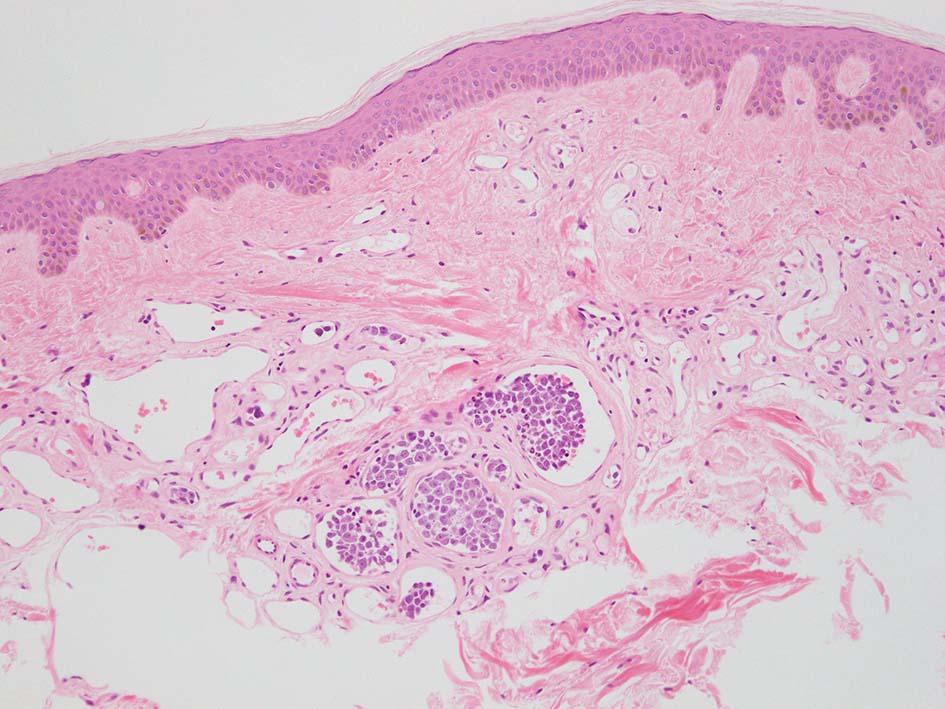

この症例は皮膚, cherry spotとよばれる老人性血管腫の血管内に腫瘍細胞集簇を認めた. (老人性血管腫はよい生検スポットといわれていたが, 必ずしもそうとはいえないらしい)

皮下脂肪織,細血管内の腫瘍細胞. 大型多型細胞より若干小さめの腫瘍細胞も認められる. CD20を先に染めておくと病変の有無がわかりやすい. HEだけで安易に「病変なし」としないほうがよい.

ランダム皮膚生検